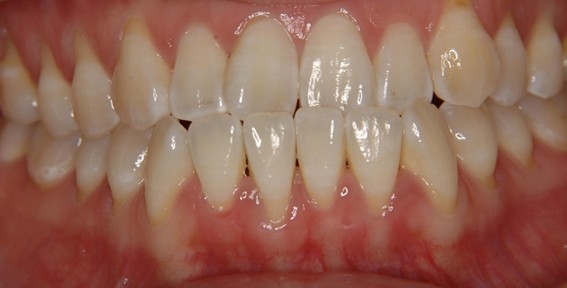

| 主訴 | 口元がでている、口が閉じずらい、上の歯と下の歯のがたつき、顎がない。 |

| 治療内容 | 上下のワイヤー矯正を行いました。 |

| 想定されたリスク | 知覚過敏・咬合痛・歯肉退縮・歯髄壊死・歯髄充血のリスクがありました。 |

以前骨切りを勧められたことがあるという方でしたが、抜歯矯正で口元の突出や顎のしわを改善しました。上唇の厚みや頬の高さを考慮し、老けた印象にならないよう配慮。お顔全体のバランスと年齢に合わせた治療を行いました。